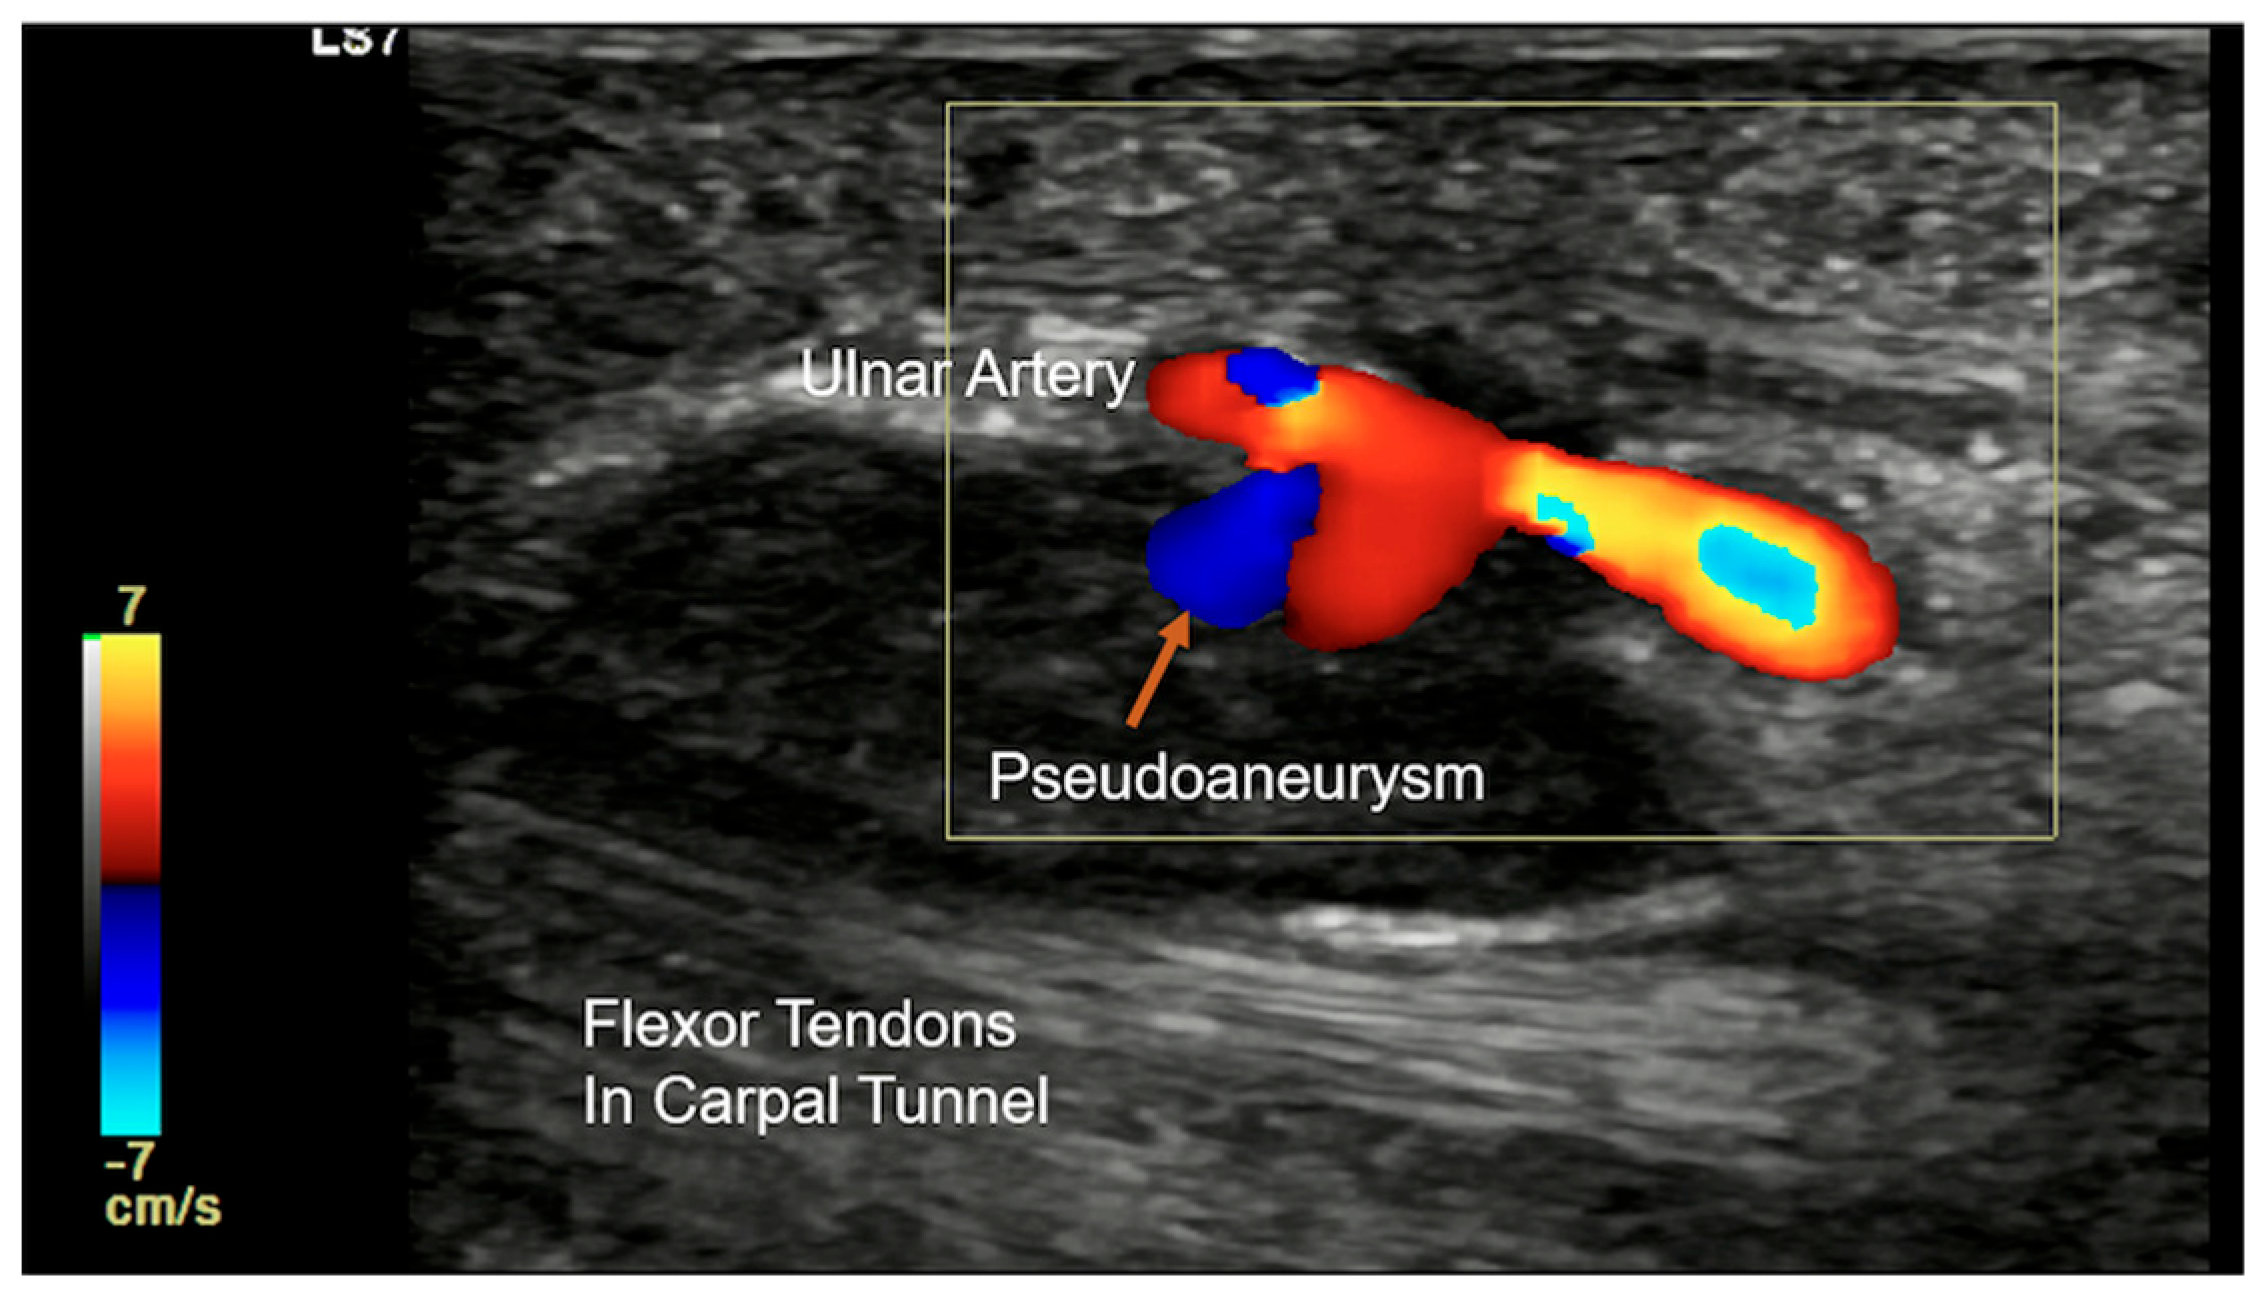

| Vascular Abnormalities (Aneurysms, Thrombosis, AVM) | Hypoechoic/anechoic mass with vascular flow (aneurysms) or absent flow (thrombosis) on Doppler. | Thrombosis: Low or high signal in vessel lumen on T1/T2 (depending on stage). Aneurysms: Well-circumscribed lesion with potential signal voids from high flow. |

- Carr, M.P.; Becker, G.W.; Taljanovic, M.S.; McCurdy, W.E. Hypothenar hammer syndrome: Case report and literature review. Radiol. Case Rep. 2019, 14, 868–871. [Google Scholar] [CrossRef] [PubMed]